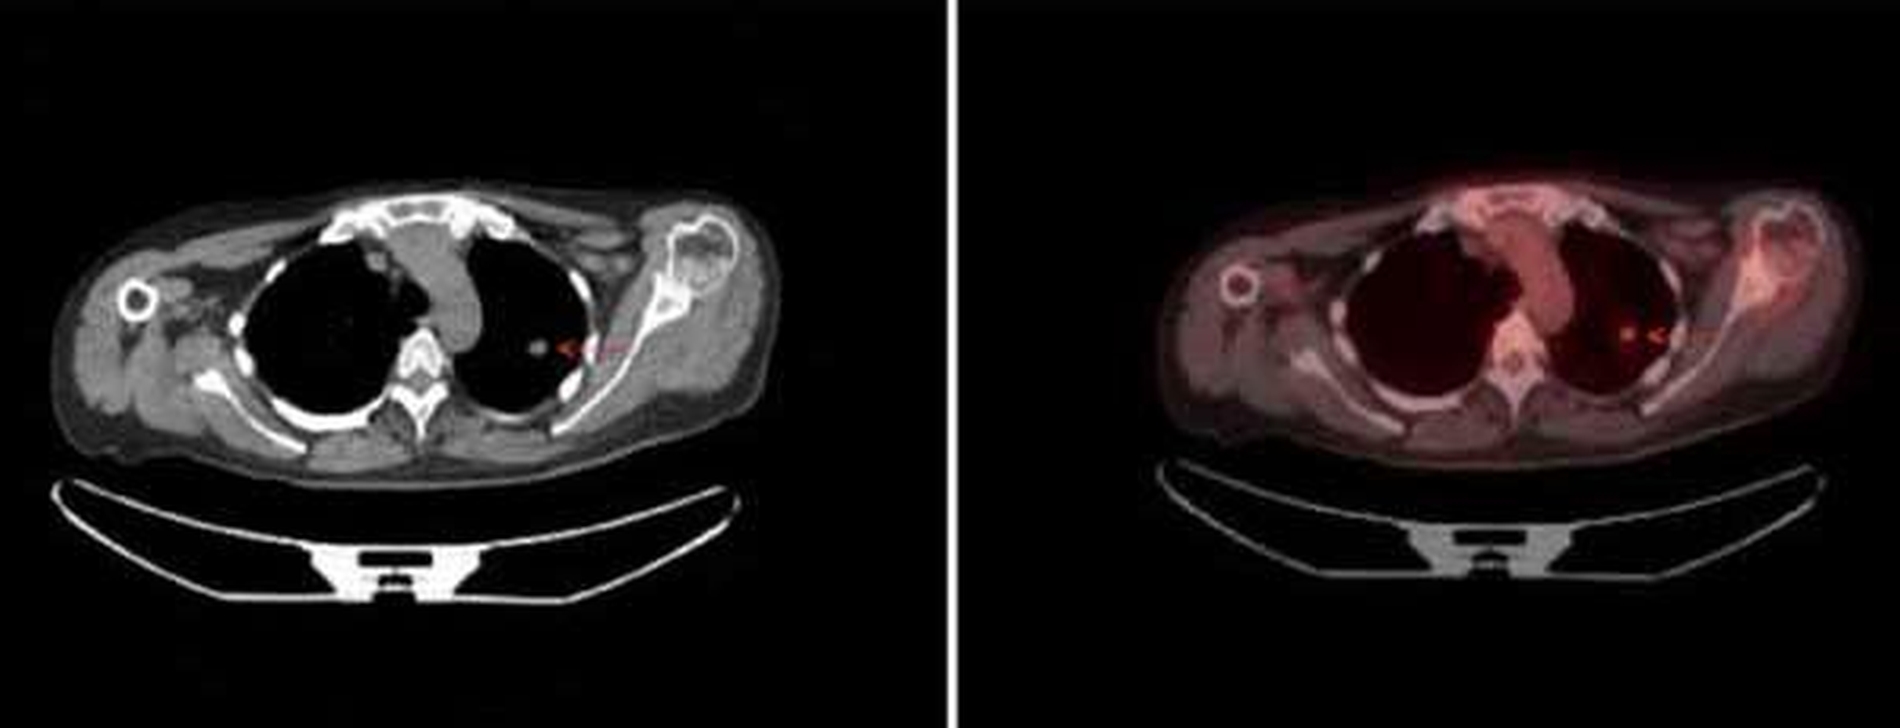

Allerdings ergab sich in der Bildgebung inklusive 18F-2-Fluor-2-desoxy-D-glucose (FDG)-Photonen-Emissions-Tomographie / CT (PET/CT) der dringende Verdacht auf eine Metastase im linken Lungenoberlappen (Abbildung 2).